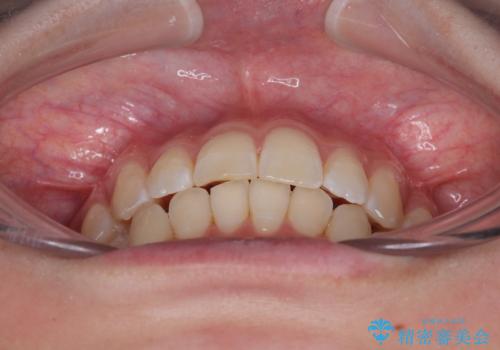

- 上下前歯の重なりを気にして来院された患者様です。

安価なインビザラインパッケージを用いての治療を希望されており、デコボコの程度が中等度であったため、インビザライン・モデレートを用いて矯正治療を行うこととしました。